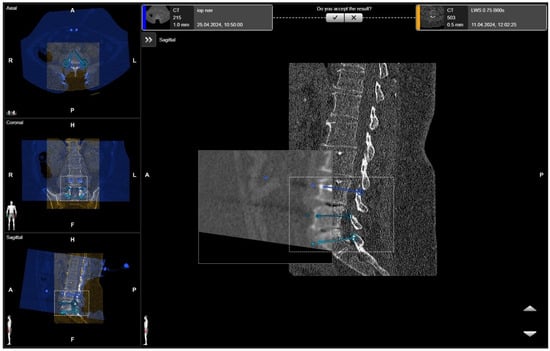

After selecting a region of interest (ROI), the iCT scan was merged with a preoperative scan. A rigid fusion was performed, and in cases of instability of the spine due to a tumor or fracture, as well as in cases of longer constructs, elastic fusion was performed (Figure 7 and Figure 8). In selected cases with longer thoracolumbosacral constructs, two scans were performed, with repositioning of the reference array to avoid compromising accuracy for levels far from the reference array. After fusion of the scans, the planned screw trajectories were checked and corrected as necessary (Figure 9) [4].

Figure 7. Rigid fusion of selected ROIs of two planned segments for stabilization (same patient as in Figure 1 and Figure 2).

Figure 8. Elastic fusion of the preoperative CT and the iCT scan with preplanned screw trajectories in a fracture at the thoracic–lumbar junction, performed due to instability.